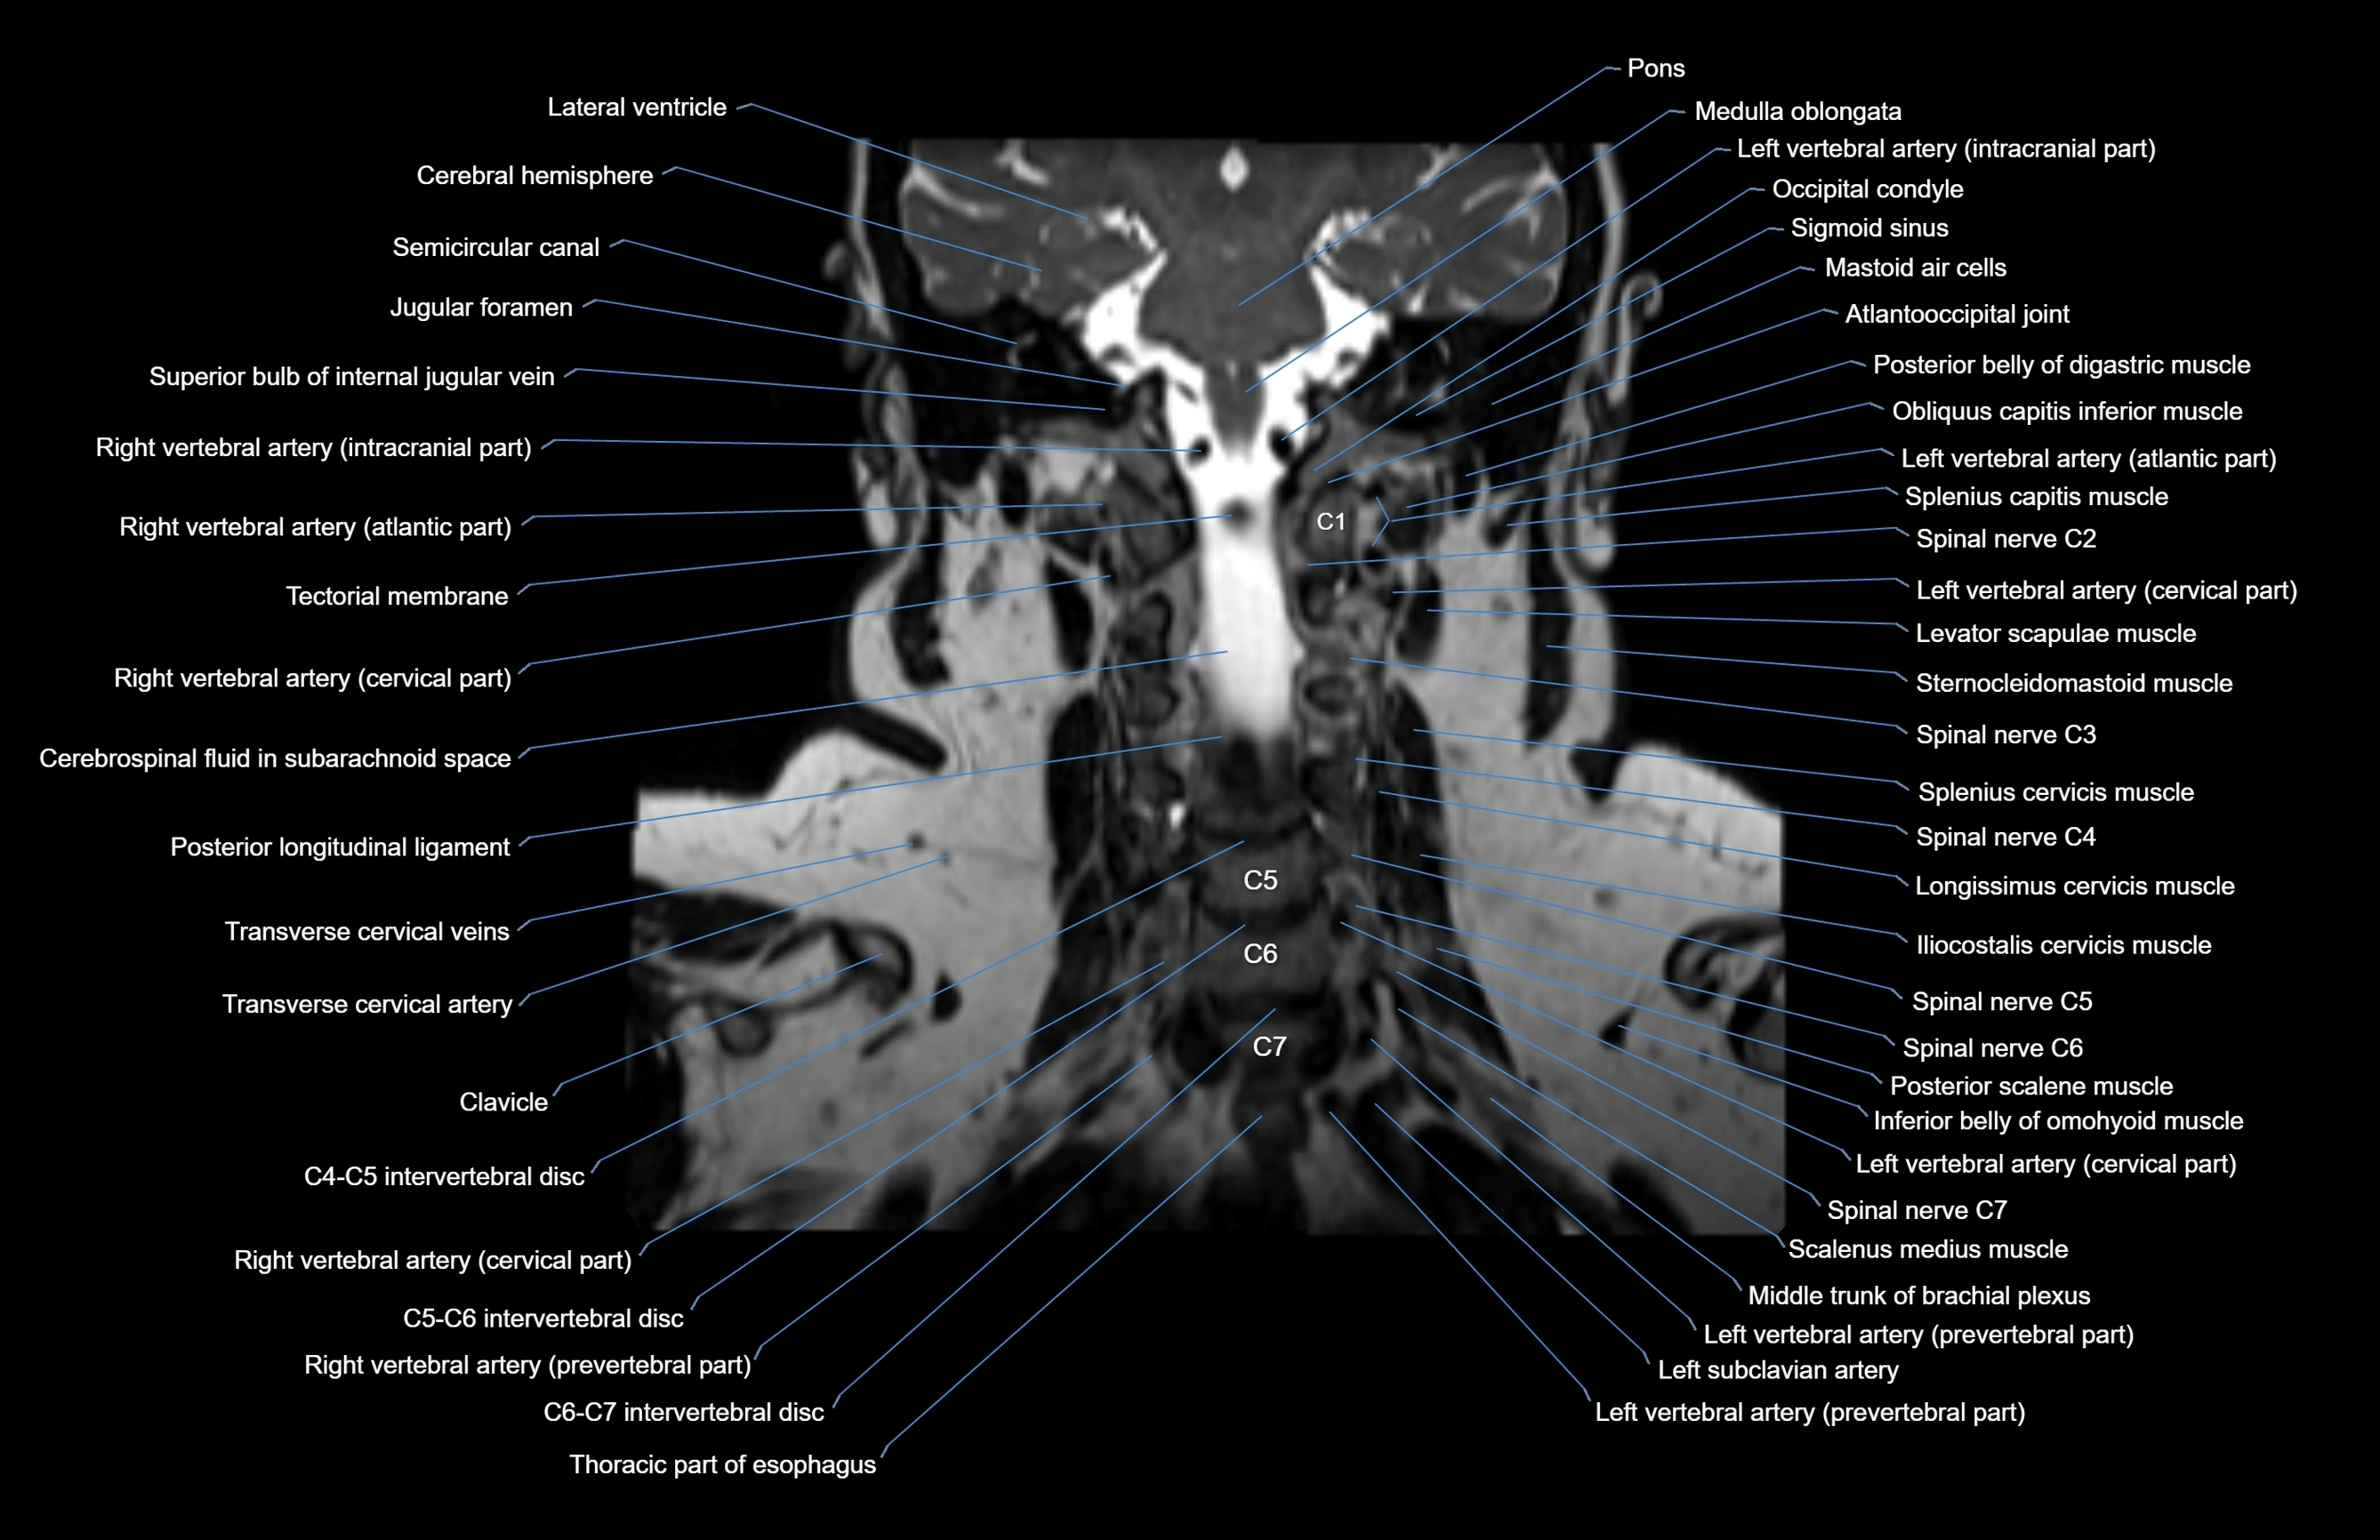

- Clavicle

- Iliocostalis cervicis muscle

- Inferior belly of omohyoid muscle

- Left vertebral artery (atlantic part)

- Left vertebral artery (cervical part)

- Levator scapulae muscle

- Longissimus cervicis muscle

- Occipital condyle

- Posterior longitudinal ligament

- Right vertebral artery (atlantic part)

- Right vertebral artery (cervical part)

- Semispinalis cervicis muscle

- Spinal cord

- Splenius capitis muscle

- Splenius cervicis muscle

- Sternocleidomastoid muscle

- Superior bulb of internal jugular vein

- Tectorial Membrane

- Thoracic part of esophagus

- Transverse cervical artery